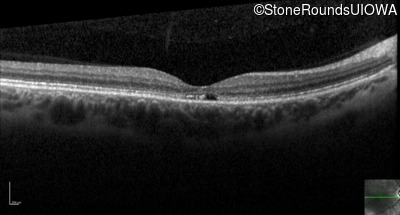

Optical Coherence Tomography - Right - 20/20 -1

Exemplar / OCT Stack